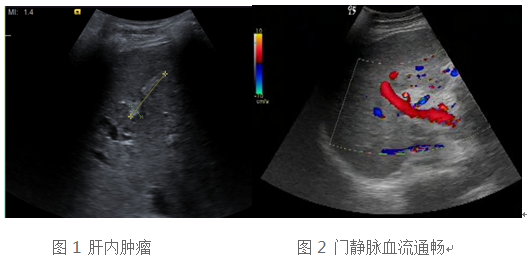

病例一:

59岁的肝硬化肝癌患者白先生,入住我院移植科,准备肝移植手术,术前完成相关组织配型及手术风险评估,患者及移植团队专家担心的是,是否有癌肿肝外转移,心脏扩大能否耐受手术。通过全面系统的超声检查,我们得出的结论是虽然患者肝内有肝癌占位(图1),但是肝外脏器及门静脉内部未见转移(图2),根据欧洲肝病协会(EASL)发布的《2015 年肝移植临床实践指南》,属于肝移植手术的适应症。患者超声心动图提示左心室及左心房扩大,但是心脏收缩功能尚正常,所以能耐受肝移植手术。